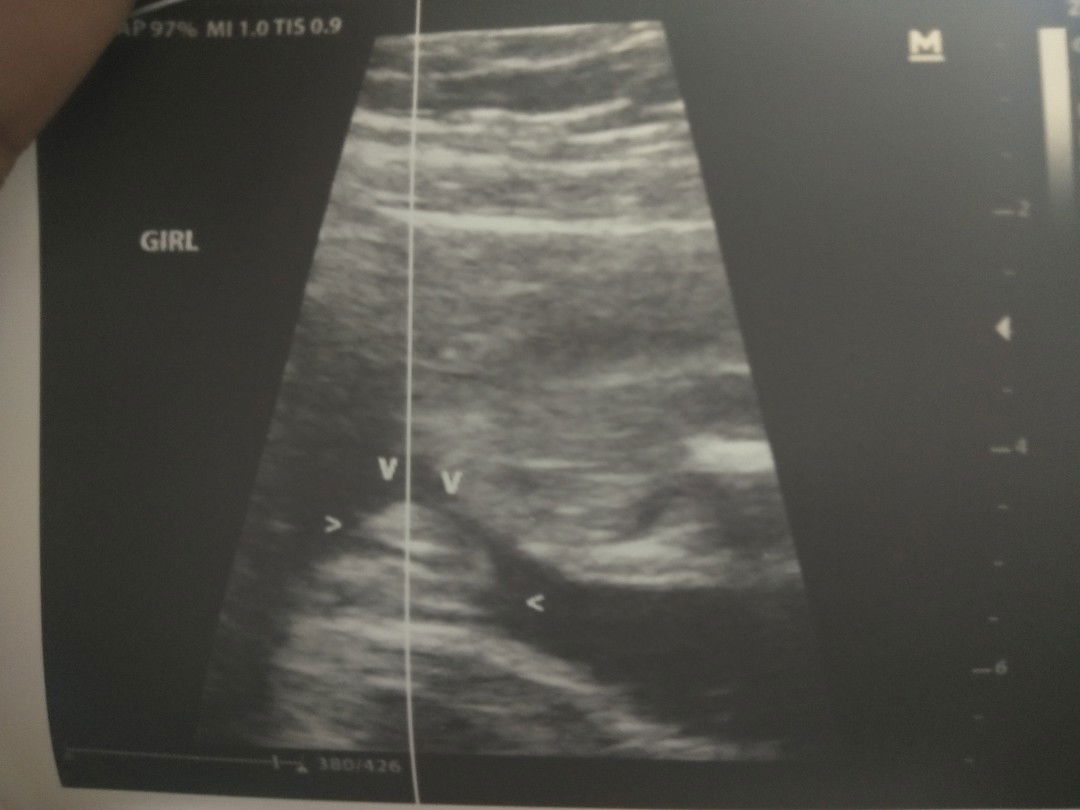

It's a girl!!!

Share ko lang mga mamsh!!! Sa last post ko about gender ang dami nanghula na it's a SHE, and yes mga mamsh ShE is!!! I thank God for a healthy baby girl inside my womb. Kahit na suhi ang position nya still not yet worried since 6 months plng si baby. We still hve tome to talk to her to have a good positioning for her birth. Thank God sa lahat! Godbless us all mommies! ??? #Sharethelove